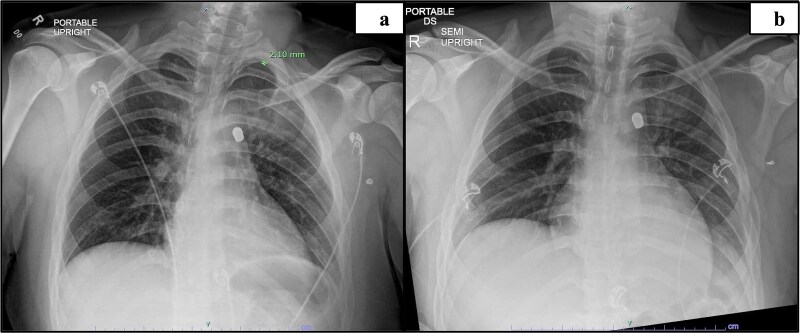

本病例研究报告了一名17岁的男性,在左上臂受枪伤后接受了机器人辅助的异物取出术,该枪伤导致子弹穿过胸壁直接停在主动脉肺窗处的纵隔。异物靠近大血管给术前成像和手术计划带来了挑战,因此成为这个独特病例的焦点。最终,机器人辅助取出子弹的手术成功了,没有损坏周围的结构。到目前为止,还没有关于机器人在这个解剖部位进行异物清除的研究报道。

This case study reports on a 17-year-old male that underwent robotic assisted foreign body removal after sustaining a gunshot wound to the left upper arm that resulted in the bullet traversing through the chest wall to stop directly in the mediastinum at the aortopulmonary window. The proximity of the foreign body to the great vessels introduced challenges for preoperative imaging and surgical planning, thus becoming the focus of this unique case. Ultimately, the robotic-assisted removal of the bullet was successful without damage to the surrounding structures. To date, no known study has reported on robotic foreign body removal at this anatomic location.